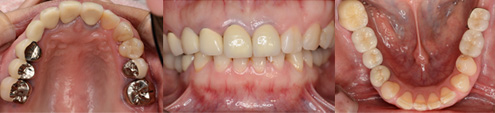

43歳 女性

主訴 奥歯で物が咬めない

治療内容 歯周病治療 咬合治療 インプラント治療 歯内治療(根の治療)

治療後